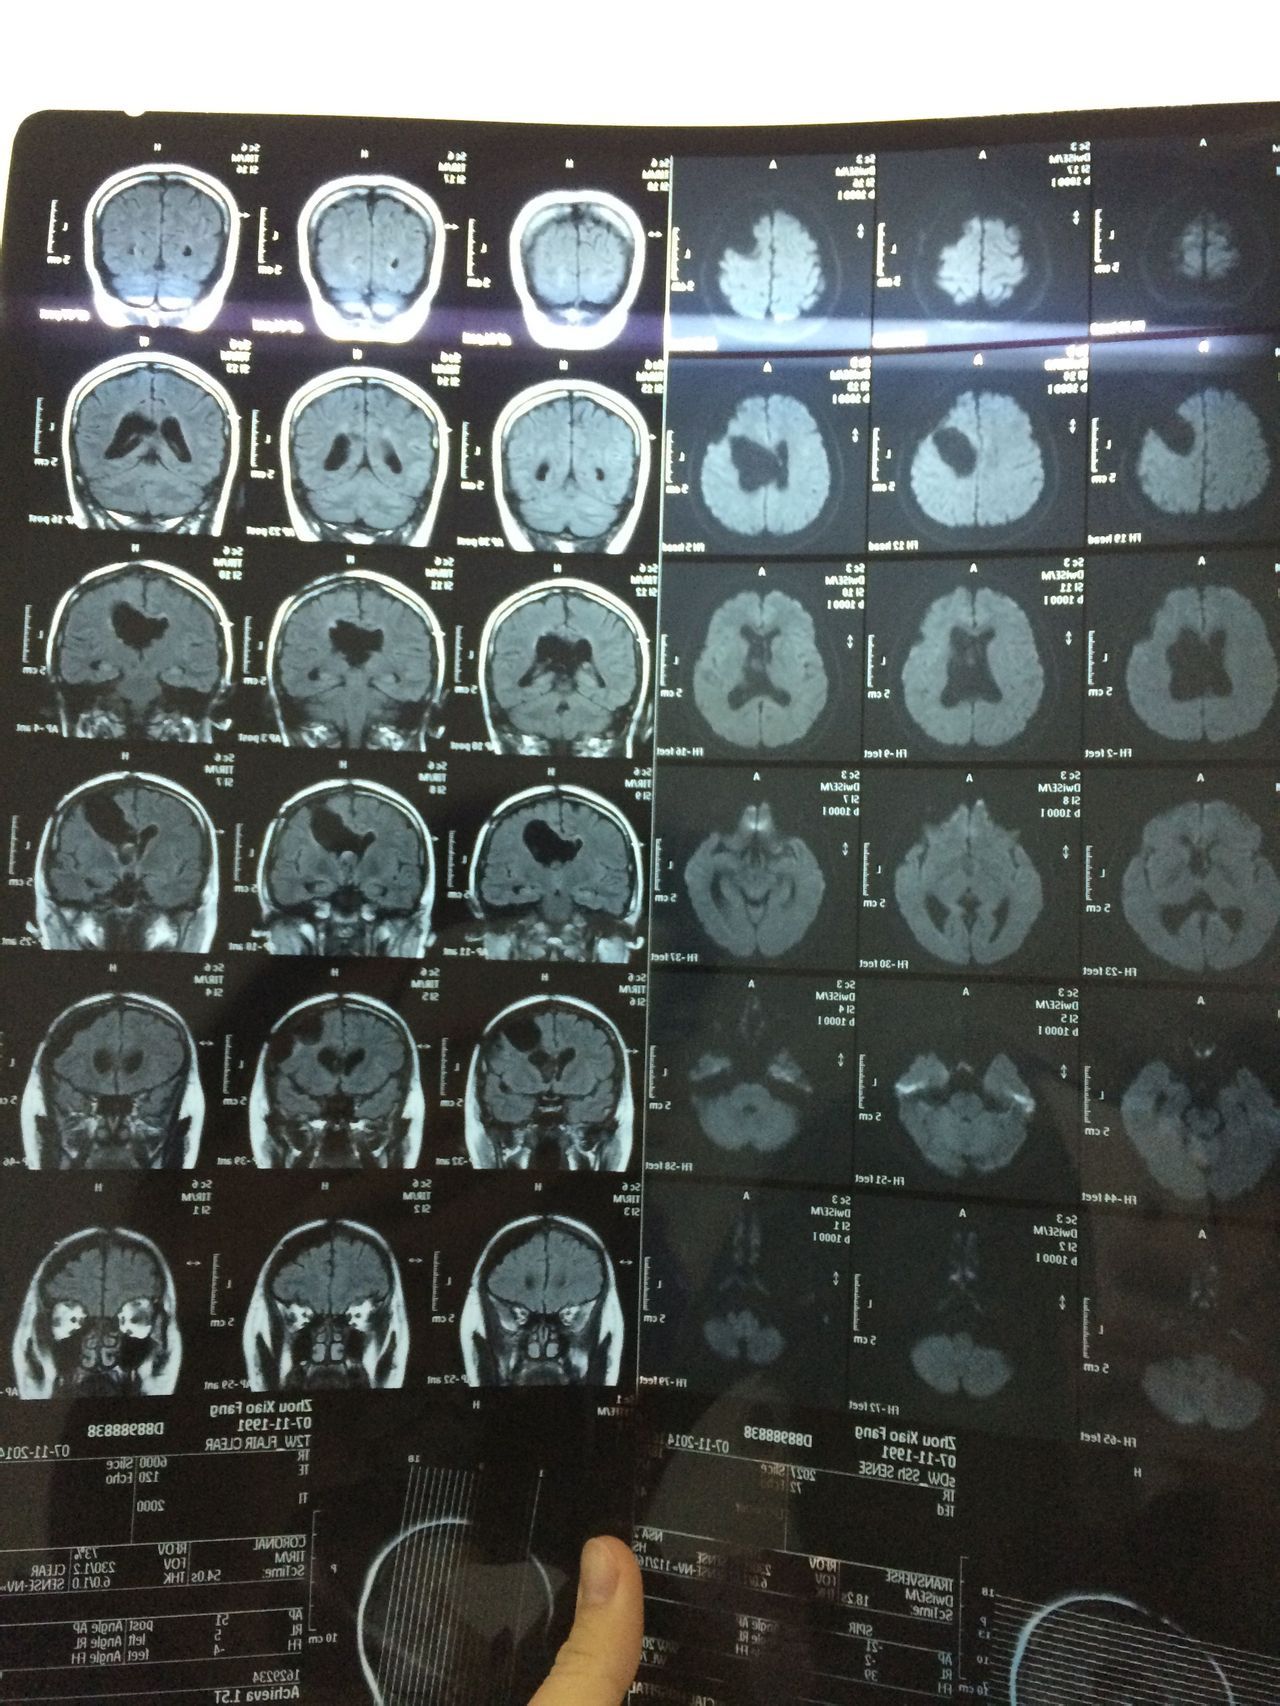

患者女,23岁。2011年9月脑胶质母细胞瘤外科手术,术后无措施,半年复查核磁共振。2013年5月做伽马刀治疗。持续每半年复查核磁共振。    患者身体状况良好,生活上基本没有问题。偶尔出现头晕不排除感冒等因素,但是如果晃到脑部,会有头晕或疼痛感出现。    另外,患者在手术前,经期不规则,大体上一两个月一次,时间不确定。术后,经期不规则更严重,2-3月一次,时间也不固定,但是量少,时有淤血,做过性激素水平检查及妇科常规,正常。2014年11月复查报告麻烦查看附件。    疑问:    1、患者现在需要积极的治疗吗?    2、患者的脑积水严重吗?在这三年内,脑积水虽有波动(增减),但是大体上在一个程度,较稳定。需要做颅内压检查吗?    3、患者现在适合备孕吗?(一直在避孕,暂时未知是否影响怀孕。)这个问题比较复查,还希望各位专家能给予分析利弊。(谢谢!)    3.1、怀孕各个阶段对患者的肿瘤是促进还是抑制作用是否有临床经验供参考?是否可以做一下评估。    3.2、怀孕各个阶段是否会患者造成负担,使其脑积水等加重?    3.3、如果现期不适合备孕的话,有存在“等待”的必要?也或许以后也是这种情况?    最后,很感谢各位专家百忙之中能够为本人了解这份信息。本人是患者的丈夫,发这个问题上来,只是想了解一下情况。虽然我们都很希望能够有爱的结晶,但是我十万分不愿意我的爱人去冒险。各位专家,希望能给予详细的说明和建议。    衷心的祝福你们。

根据影像可以看到脑室轻度扩大,脑胶导劣报质母细胞瘤恶性程度非常高,且术后复发率很高,乔实再加上已经做了伽马刀,对垂体功能影响无法判断。目前治疗口服替莫唑胺治疗,是否可以怀孕,还们院是建议咨询产科医师,详细的检测体内激素水平。